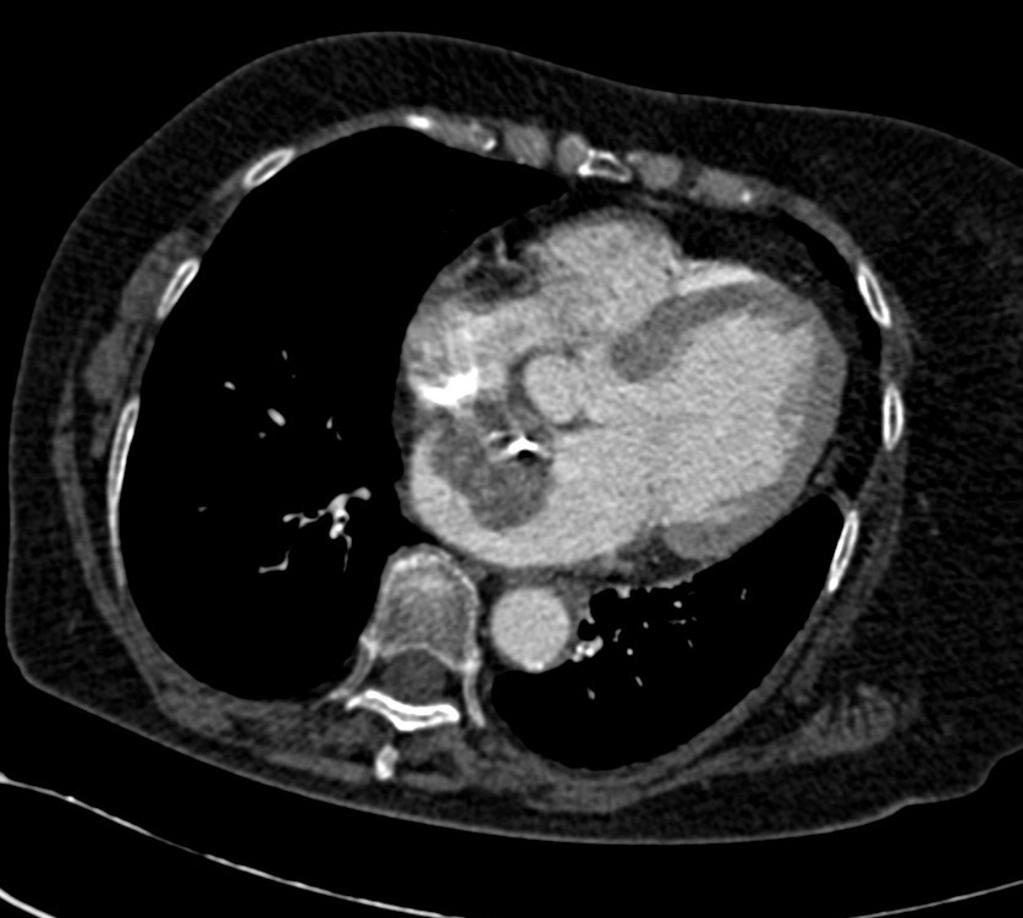

Тромб в правом предсердии

Тромб в правом предсердии 115 фото